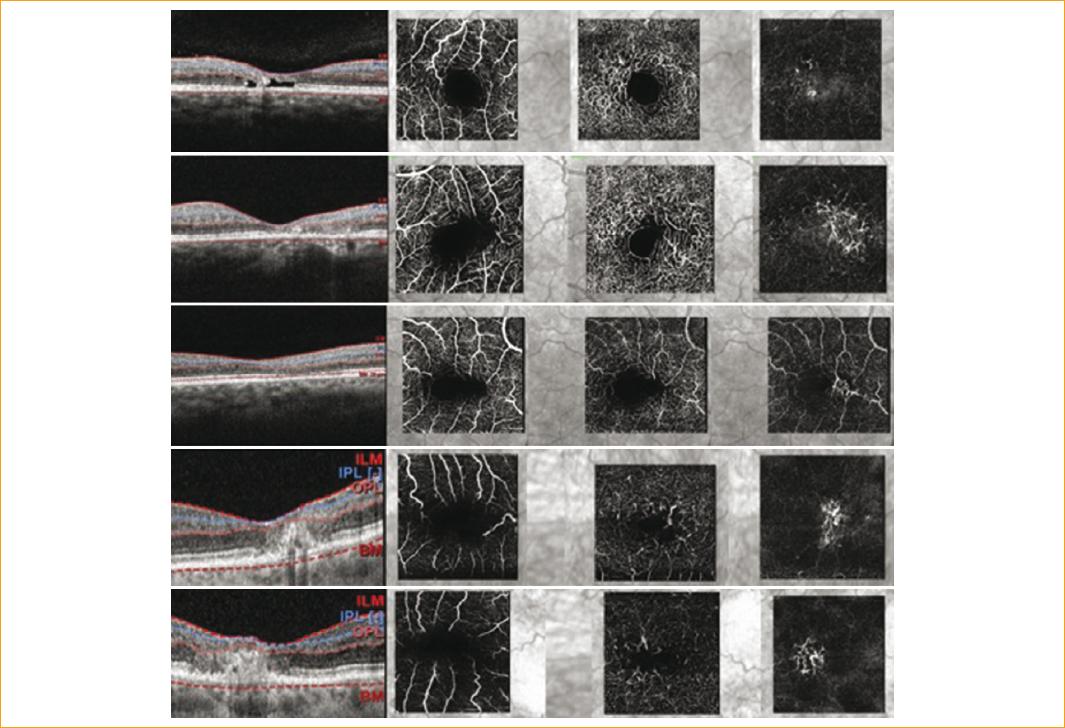

Nueve ojos (21%) presentaron neovascularización coroidea. Cuatro pacientes presentaron membrana neovascular franca, a los que se les indicó terapia con antiangiogénico intravítreo. Los cinco ojos restantes (55%) presentaron neovascularización subclínica, ya que no se observaron datos de neovascularización por clínica, OCT ni FAR, solo se detectó en la capa avascular de la OCT-A (en estos pacientes se descartaron artefactos). Los pacientes con neovascularización subclínica no presentaban mayor afección visual (LogMAR 0.3) (Figs. 1 y 2).

Figura 1 Imágenes de angiografía por tomografía de coherencia óptica de cinco pacientes con neovascularización evidenciada en el plexo avascular. La primera columna son imágenes de corte central macular, la segunda del plexo vascular superficial, la tercera del plexo profundo y la cuarta de la capa avascular.

Figura 2 Imagen superior: angiografía por tomografía de coherencia óptica (OCT-A) del ojo derecho, plexo superficial con disminución de la densidad vascular leve, en el plexo profundo se observan vasos telangiectásicos perifoveales. Imagen inferior: OCT-A del ojo izquierdo, en el plexo superficial y profundo vasos telangiectásicos, pérdida de densidad vascular y en la capa avascular neovascularización.

El plexo vascular más afectado fue el profundo, en un 94%. En el 35% de los pacientes se logró visualizar vasos en ángulo recto (Fig. 3). Las características morfológicas que observamos en los vasos afectados fueron: un engrosamiento con dilataciones focales y, solo en el 33%, lesiones aneurismáticas con morfología (Fig. 3).

Según el estadiaje por OCT-A se encontró: el 21% en estadio 1, el 38% en estadio 2, el 32% en estadio 3 y el 9% en estadio 4. No se presentaron pacientes con características del estadio 5.

Los hallazgos más comunes en la retina neurosensorial por imagen de OCT macular fueron: puntos hiperreflécticos en el 86%, discontinuidad complejo Bruch/EPR y línea elipsoide en el 81%, cavitaciones en el 54% y neovascularización coroidea en el 9% con engrosamiento macular por líquido intrarretiniano (Fig. 4). El grosor macular central (GMC) promedio fue de 236 um y no se encontró una relación significativa entre este y la agudeza visual (p = 0.29).